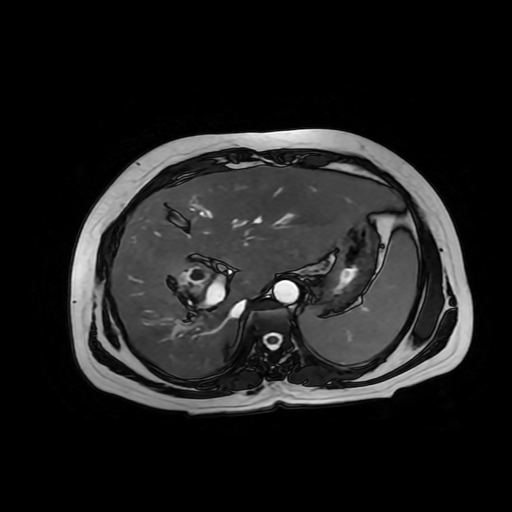

Paciente de sexo femenino, de 56 años de edad, refiere dolor en cuadrante superior derecho, indica que le realizaron colecistectomía de hace mas o menos 7 años, presenta cuadro de ictericia de 6 meses de evolución. Médico tratante le solicita estudio de Resonancia de vías biliares (Coilangioresonancia)

Se prepara a paciente previo a ingreso a zona 4 del área de resonancia magnética, paciente se presenta con catéter en región anterior del antebrazo, se utiliza bobina de abdomen de 16 canales y se procede a obtener localizadores en los tres planos, para luego adquirir imágenes en diferentes planos, en secuencias espin echo, eco de gradiente, secuencia de difusión. Se utiliza medio de contraste hepatoespecifico con dosis sugerida por fabricante.

Se observa dilatación de las vías intra hepáticas a expensas de sus ramas hepáticas derecha, anterior y posterior, hepática izquierda y hepática común. El hepático común da la apariencia de estar anastomosado a un asa de intestino, lo que sugiere la posibilidad de una cirugía entero biliar.